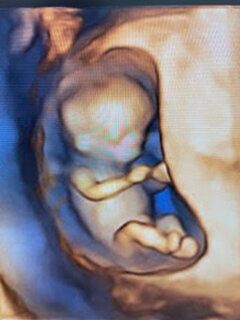

3D, 4D, and 5D Imaging

Gallery